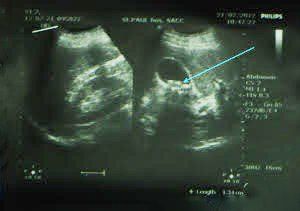

- Siêu âm: Kỹ thuật này sử dụng thiết bị đầu dò và sóng âm thanh an toàn để tạo ra hình ảnh của túi mật, giúp nhận diện sỏi mật. Quá trình thực hiện siêu âm hoàn toàn không gây đau đớn.

Một bệnh nhân nữ 54 tuổi không có tiền sử bị đau hoặc sỏi túi mật được phát hiện trước đó vào viện vì cơn đau bụng dữ dội ở khu vực trên rốn và dưới sườn bên phải. Quá trình khám lâm sàng cho thấy khả năng viêm tuỵ cấp, trong khi siêu âm bụng phát hiện sỏi nhỏ ở túi mật, kết quả xét nghiệm máu cho thấy nồng độ amylase vượt quá 3000 đơn vị.